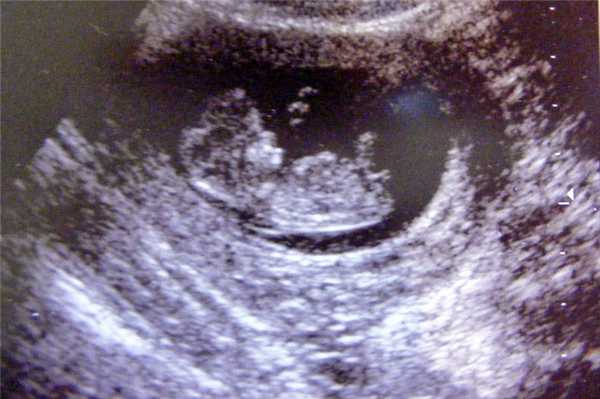

Фото УЗИ ребенка на 12 неделе беременности

Это очень важный период, поскольку гинеколог направляет женщину на первый скрининг. Он включает УЗИ и биохимический анализ венозной крови на гормоны. Ультразвуковое исследование в это время очень информативно и позволяет определить ряд врожденных патологий.

Визуально на фото видны такие особенности плода:

- хорошо просматриваются глаза (они обычно закрыты), нос малыша и другие черты лица;

- ребенок может открывать рот и глотать околоплодные воды;

- размеры плода все еще непропорциональны, но все части тела сформированы;

- в области половых органов происходит гипотрофия мошонки у мальчиков или гипертрофия половых губ у девочек (по этим признакам можно определить пол);

- движения плода хаотичные.

Скрининг на 12 неделе позволяет определить ряд патологий внутриутробного развития. Для этого аппарат УЗИ проводит ряд автоматизированных замеров. На основе этих измерений производят оценку формирования плода.

В этот период обязательно определяют такие параметры: